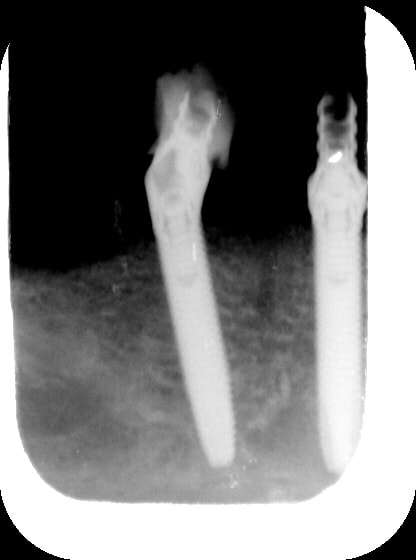

PJ les RX du jour

Ginette1 m6wcq1 - Eugenol

Ginette2 fmx7wf - Eugenol

rx du haut...8 mois après...

Gin8m1 wfymdg - Eugenol

Gin8m2 rdbaga - Eugenol

Gin8m3 zsapdx - Eugenol

l' implant en 25 aurait pu etre un peu plus distalé....mais plus court...